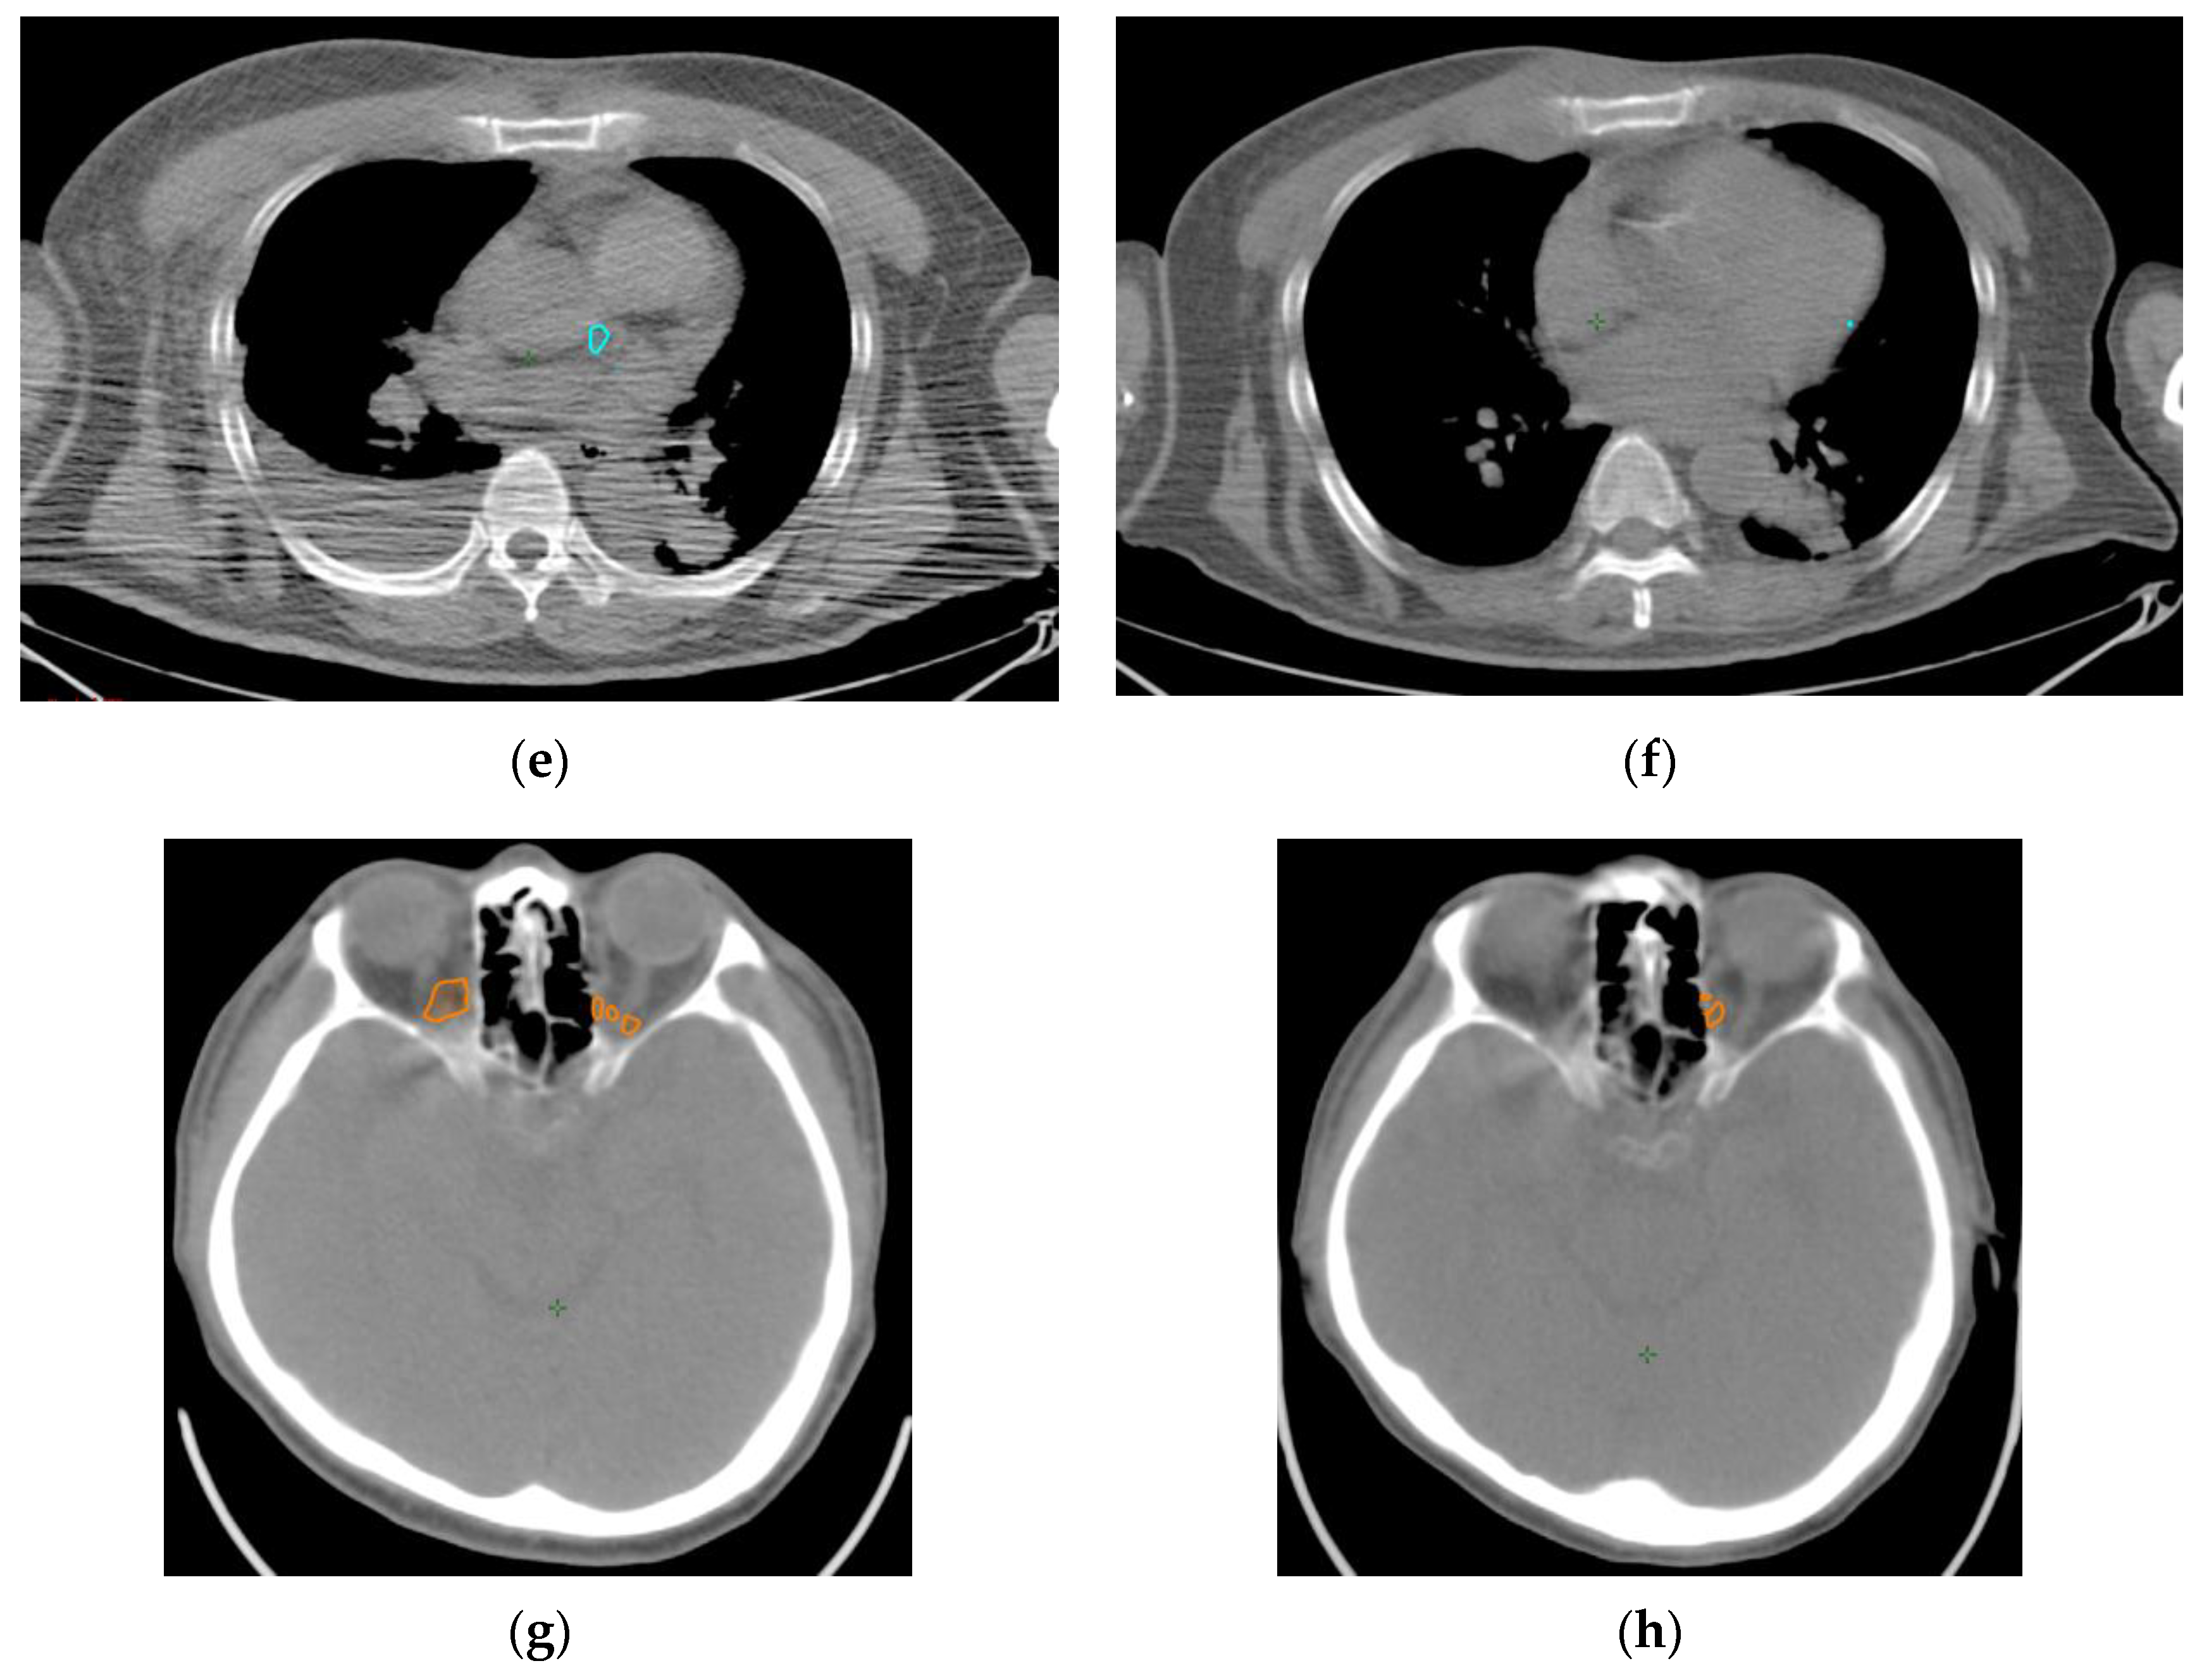

4. Materials and Methods